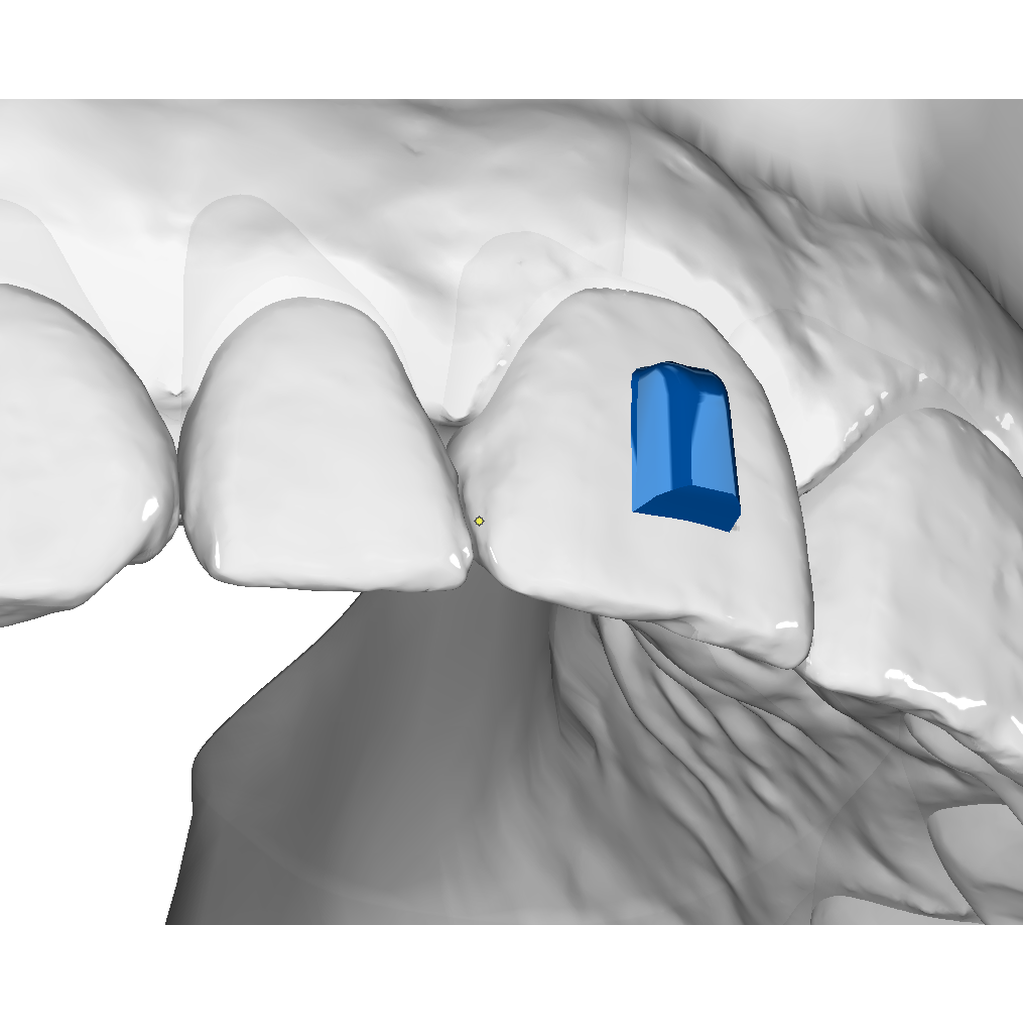

Vertical Attachment Template for Aligner Therapy

The vertical attachment is the workhorse of aligner biomechanics. Its vertical orientation provides the leverage needed for derotation, full bodily movement, and demanding distalization sequences — making it an essential part of any comprehensive aligner case.

✔ Derotation & bodily movement — vertical geometry delivers the control needed for complex 3D tooth movements

✔ Semi-sequential distalization — reliable anchorage for staged posterior movement

✔ Four size options — from 3×2 mm to 6×3.5 mm to match any tooth and indication

✔ Digital O3P template — ready to place directly in OnyxCeph